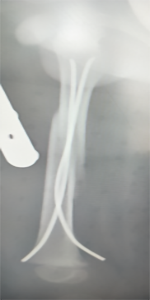

儿童股骨干骨折的微创弹性髓针固定技术:

儿童股骨干骨折的微创弹性髓针固定技术(术后伤口外观仅缝合两针)